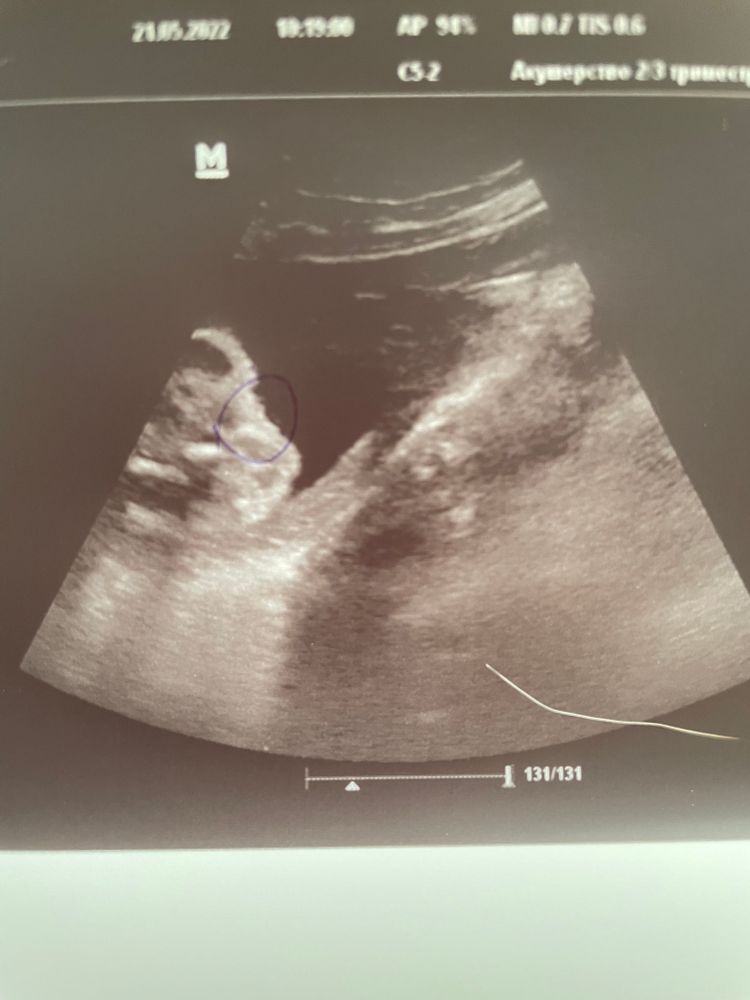

Александра Серова, да, девочку на всех УЗИ начиная с первого скрининга. В последнем УЗИ (20 недель) тоже сначала посмотрели пол - девочка. А потом начали мерить бедренную кость, а он раздвинул ножки, а там: